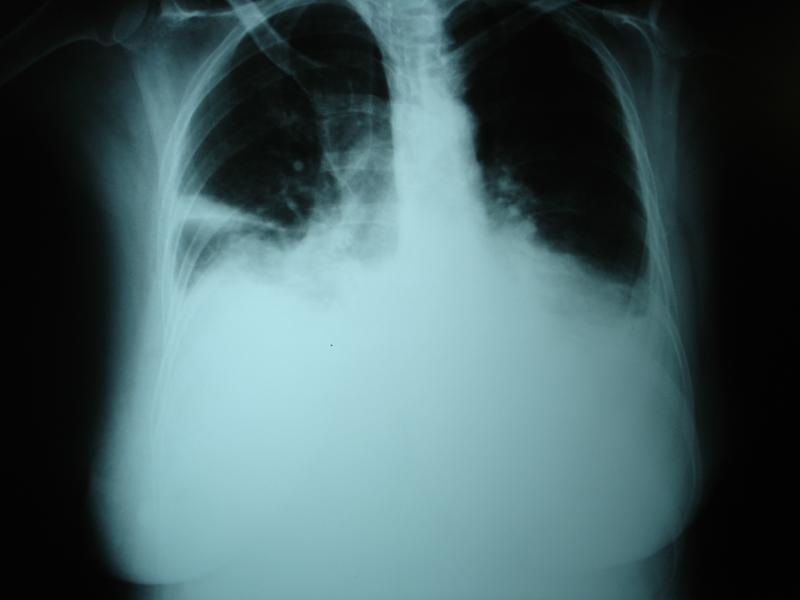

PLEASE-2 is a prospective exploratory pilot study assessing the effects of unilateral effusion and drainage on both hemidiaphragms using advanced quantitative bedside ultrasonography. The researchers included individuals with symptomatic unilateral pleural effusion undergoing therapeutic drainage.

Twenty individuals (mean age 68.9 years, 12 females) participated in the study. Contralateral hemidiaphragm excursion went above the ipsilateral excursion and reference values (p≤0.001 for all) during tidal breathing.

Abnormal shape (n=12) and paradoxical movement (n=9) of the ipsilateral hemidiaphragm resolved in all participants, while tidal excursion of the contralateral hemidiaphragm normalized, after drainage (mean volume 2,121 ml). Relief of breathlessness following drainage was associated with improvement in ipsilateral hemidiaphragm excursion (r, 0.556; p=0.031).